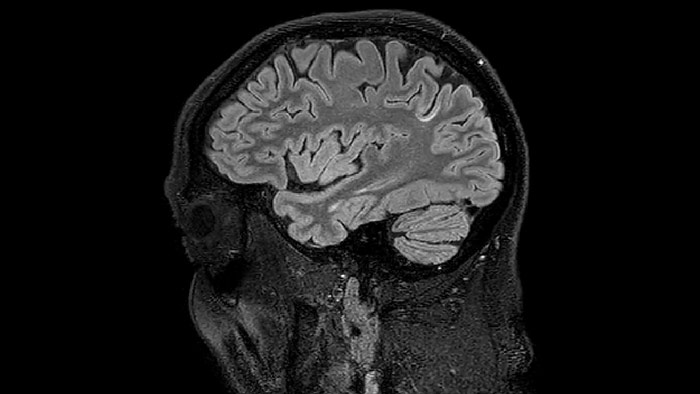

Sagittal 3D FLAIR with 0.3 mm3 voxel volume acquired in 5:12 min. using Compressed SENSE showing a (juxta)cortical MS lesion.

He says the accelerated scanning is achieved via the use of Compressed SENSE and MultiBand SENSE. “We can use Compressed SENSE acceleration factors of about 10 on a 3D FLAIR for instance, which is quite remarkable compared with what we saw with the Achieva. With 3D FLAIR, we can push the spatial resolution to 0.3 cubic mm and it works. Previously, our 3D FLAIR scans lasted about 8 minutes, but now with Elition they are five minutes. The SNR is also visibly better. Our SWI and QSM scans look fantastic. Also, since a lot of neuroimaging is EPI based, using the MultiBand SENSE technique can increase temporal resolution and make it possible to run complicated DTI scans relatively quickly.”

of limiting MWI to the brain, even without the cerebellum, we can now spend about the same amount of time and scan the whole brain and the cervical spinal cord, which is a huge boost for us.” Dr. Rauscher says, “For MWI we perform 3D T2 with 32 or more echoes. This used to take a long time, but with Compressed SENSE we can decrease this to ten minutes for the whole head. Because of the large field of view (FOV) on the readout direction, we even get information from the brainstem, which we previously missed when we were using the GRASE approach. Having the whole head scan is nice because it has spatial resolution, orientation and FOV that are comparable to the standard 3D clinical MS scans, including the FLAIR and 3D T2, and a 3D T1 for brain volume.”